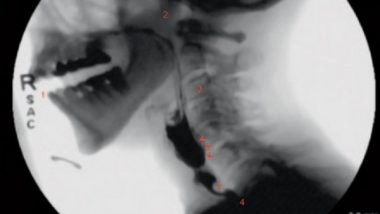

Swallowing fluoroscopy, which includes video fluoroscopic swallow studies (VFSS) and esophagrams, refers to noninvasive exams that allow physicians to examine the physiology of the throat and esophagus during swallowing to help identify what liquids and foods patients can tolerate and guide targeted treatment for patients with swallowing dysfunction.